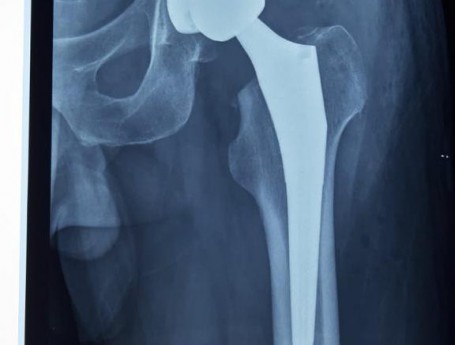

Total Hip Arthroplasty Anterior Approach